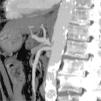

Asimismo, se observa una importante estenosis en el origen del tronco celiaco (fig. 1) con dilatación postestenótica y trombosis parcial de la luz, sugestivo de síndrome de ligamento arcuato. Se completa el estudio mediante aortografía abdominal, confirmándose la estenosis en el origen del tronco celíaco, que provoca un retraso en la velocidad del contraste por la arteria hepática común, con relleno preferente de la arteria hepática propia desde la mesentérica superior. El grado de estenosis se modifica con los movimientos respiratorios, normalizándose en inspiración y acentuándose en expiración forzada, lo que sugiere la presencia de un ligamento arcuato como causa extrínseca de la estenosis. La afectación en reposo de la luz vascular es alrededor del 50% y no existe gradiente patológico de presiones.